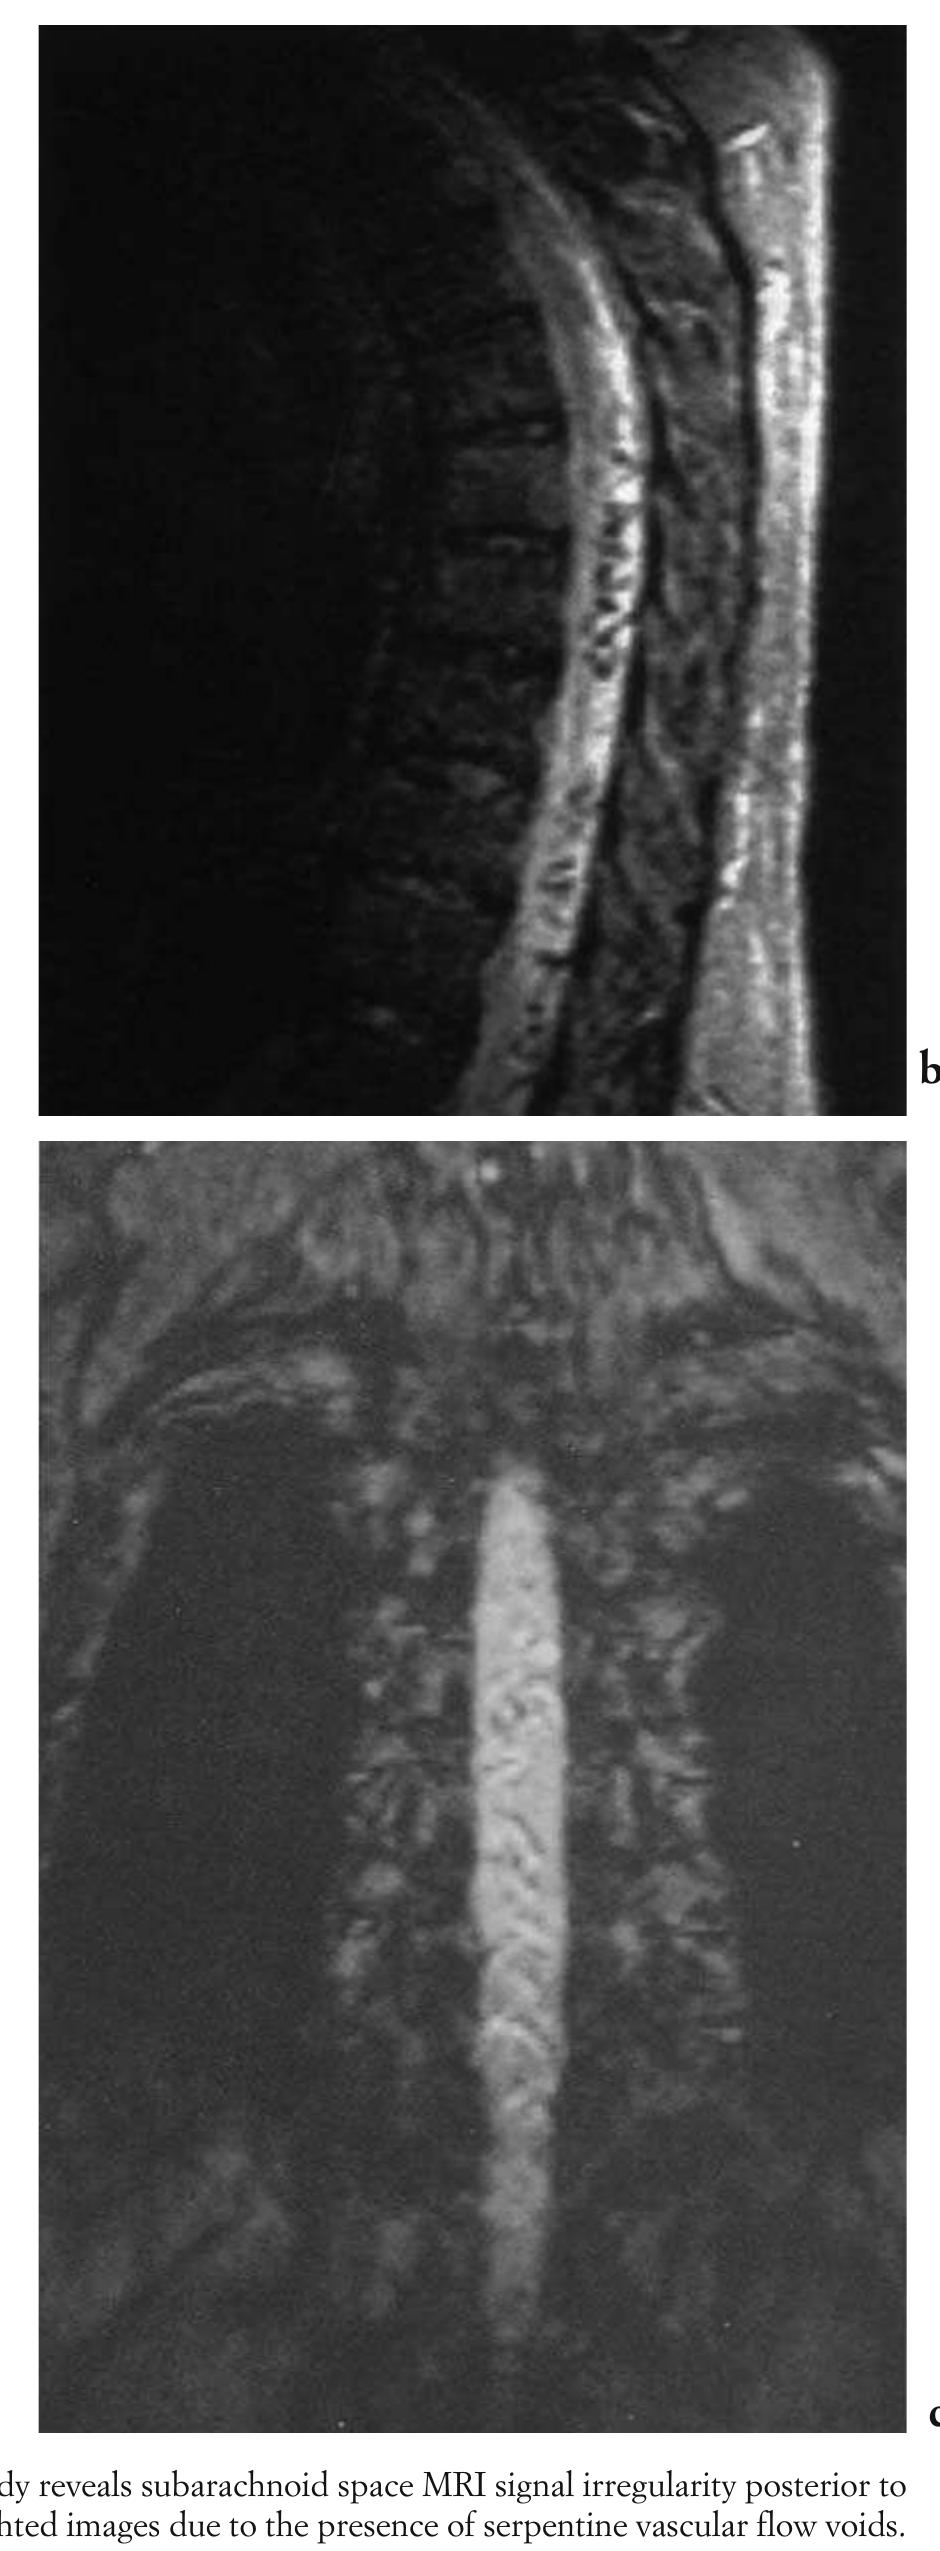

![Fig. 5.45 - Thoracic spinal dural arteriovenous fistula. The MRI study reveals subarachnoid space MRI signal irregularity posterior to the spinal cord, which becomes much more evident on the T2-weighted images due to the presence of serpentine vascular flow voids. [a) sagittal T1-weighted MRI; b) sagittal T2-weighted MRI, c) coronal T2-weighted MRI].](https://figures.academia-assets.com/35610716/figure_445.jpg)